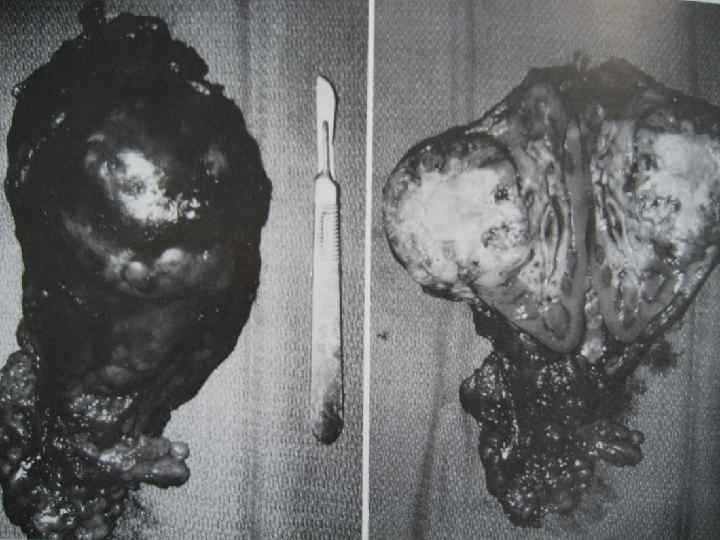

Опухоль почки Лечение • Только радикальная нефрэктомия позволяет добиться хорошей выживаемости • Стандартная оперативная техника должна включать удаление фасции Герота 11

12